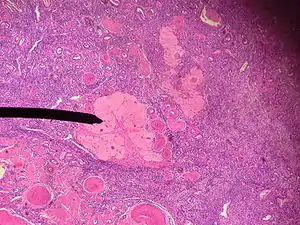

Um corpo albicans humano.

Um corpo albicans é um tecido cicatricial de um antigo corpo lúteo formado no ovário humano.

Quando não há fertilização, o corpo lúteo atinge o desenvolvimento máximo em cerca de 9 dias depois da ovocitação. Devido a degeneração de células lúteas, ele diminui de tamanho e forma uma massa de tecido cicatricial fibrótico chamada de corpo albicante (ou corpo albicans). A produção de hormônios, como a progesterona, cai simultaneamente, o que adianta o sangramento menstrual.